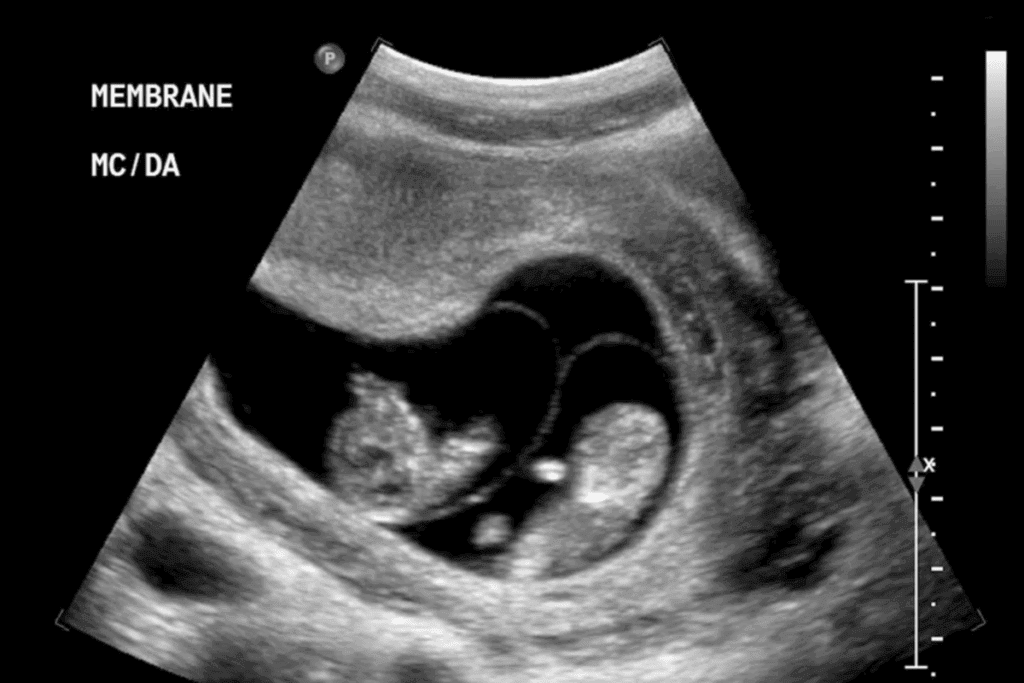

Ultrasound 14 Weeks Twins: Determining Chorionicity

At 14 weeks, an ultrasound checks if twins share a placenta. This is key for managing the pregnancy and spotting possible issues.

Dichorionic vs. Monochorionic Twin Pregnancies Explained

Twin pregnancies can be either dichorionic or monochorionic. Dichorionic twin pregnancies have two placentas and amniotic sacs. This is more common and usually safer.

Monochorionic twin pregnancies share a placenta but have separate amniotic sacs. This raises the risk of issues like twin-to-twin transfusion syndrome (TTTS).

How Chorionicity Affects Pregnancy Management and Risks

The type of twin pregnancy impacts its care. Dichorionic pregnancies face lower risks and are managed like single pregnancies, with extra checks.

Monochorionic pregnancies need closer watch because of higher risks. Ultrasounds are used to track the twins’ health and watch for TTTS.

Visual Markers on the 14-Week Twin Ultrasound

At 14 weeks, an ultrasound looks for certain signs. A thick intertwin membrane and the lambda sign or twin peak sign mean dichorionic. Monochorionic pregnancies show a thin intertwin membrane and no lambda sign.

Knowing these signs is vital for figuring out chorionicity. This helps in managing the twin pregnancy.